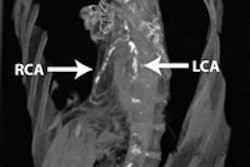

Results in 185 symptomatic patients at high risk for coronary artery disease show that CCTA is highly accurate for identifying obstructive coronary disease and for selecting patients who need revascularization. For predicting the need for revascularization, CCTA demonstrated 100% sensitivity and 100% negative predictive value, with reasonable specificity and positive predictive values. All images courtesy of Dr. U. Joseph Schoepf.

The results showed no coronary artery disease in 42 patients (23%), nonobstructive disease in 68 (36%), left main disease in four (2%), one-vessel disease in 38 (21%), two-vessel disease in 14 (8%), and three-vessel disease in 19 (10%).

In an interesting wrinkle to the study, 12% of patients, or 23, had a negative calcium score and no atherosclerosis at all, despite being symptomatic and positive on nuclear perfusion. Thirty-one patients needed CABG according to conventional catheter angiography and other parameters, and all were identified by CCTA, Schoepf said. Based on CT, 48 appeared to need a stent; 41 received them. Three patients had critical obstructive disease, but all were in very distal segments not considered amenable to intervention.

"In patients with a high likelihood of coronary artery disease, CT is an effective gatekeeper for clarifying abnormal nuclear studies; similar decisions are made by CT for identifying patients with or without the need for revascularization compared to traditional catheter angiography," Schoepf concluded. CT missed no patients who needed revascularization, yielding only seven false positives. CT also makes decisions similar to catheterization for selecting PCI versus CABG, he added.